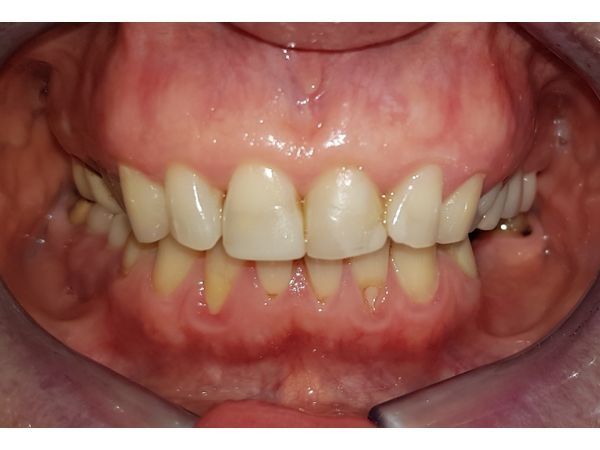

У пациентки не было некоторых жевательных зубов, на их месте стояли импланты и коронки, а дёсны вокруг отекли и кровоточили. Её также беспокоила стираемость зубов и сколы на старых пломбах.

При осмотре определялось воспаление слизистой нижней челюсти вокруг коронок и имплантов. Старые пломбы прилегали неправильно и были сколоты. Зубы наклонены в сторону полости рта, при улыбке появлялись чёрные треугольники (вместо зубов виднелась пустота).

Корни правых верхних моляров (16 и 17-го) оголились под металло-керамическими коронками и поменяли цвет.